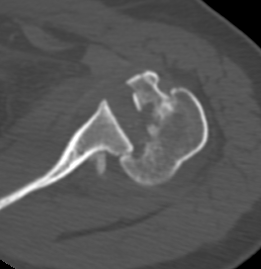

Axillary Xray

Diagnostic - humeral head posterior to glenoid with evidence of reverse Hill Sachs

CT scan

Confirms dislocation

Reverse Hill Sachs

Humeral head defect

- caused by impaction of anterior humeral head on posterior glenoid